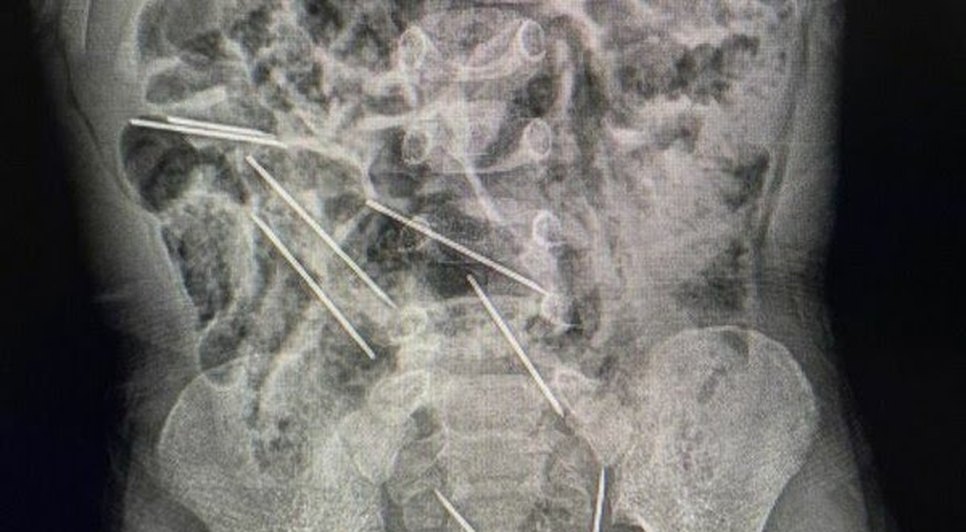

Segundo o Ministério da Saúde do país, as agulhas estavam alojadas em todo o abdômen do garoto: duas no lado direito do peritônio, três no lado esquerdo, uma na parede abdominal e outras duas entre a bexiga e o reto. A cirurgia de retirada durou aproximadamente duas horas.